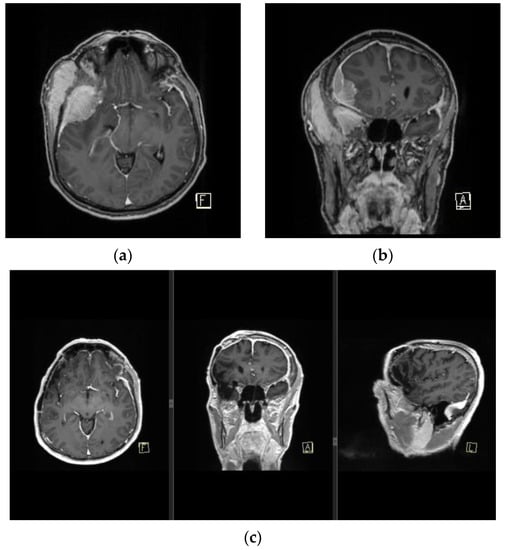

Depending on the meningioma surgical defect size, local, regional, or microvascular flaps can be implemented. Microvascular or free flaps are often the optimal solution when large defects or chronic infections are present, as well as when neurocranial structures or alloplastic materials are exposed [2,13,19,20]. Free flaps are able to provide adequate covering for implant hardware while also limiting donor site morbidity in an irradiation-impaired scalp skin quality [2,13,31]. The most common recipient blood vessels are the superficial temporal artery and vein. Blood vessels of the head and neck are commonly affected by radiation therapy, thus the choice of the recipient vessel should be carefully selected outside of the radiation segments and adequate blood supply should be verified by ultrasonography. The disadvantage of this method includes a longer duration of the operation as well as imperfect aesthetic outcomes, including the presence of contour deformities due to the robustness of free flaps [2]. In our experience, most of the patients in our cohort had a significant recurrence rate of aggressive, anaplastic RIMs, ranging from 1 to 8 recurrent meningiomas per patient (Figure 6), or were contraindicated for prolonged times in general anesthesia.

Figure 6. MRI finding of pan-meningiomatosis. (a,b) show preoperative MRI findings of an invasive anaplastic menigioma in a RIM patient due to tinea capitis radiation treatment in childhood, and prior to a wide Simpson gr I tumor resection with duroplasty and cranioplasty. (c) shows a postoperative MRI finding of the patient with a complete dural signal enhancement.